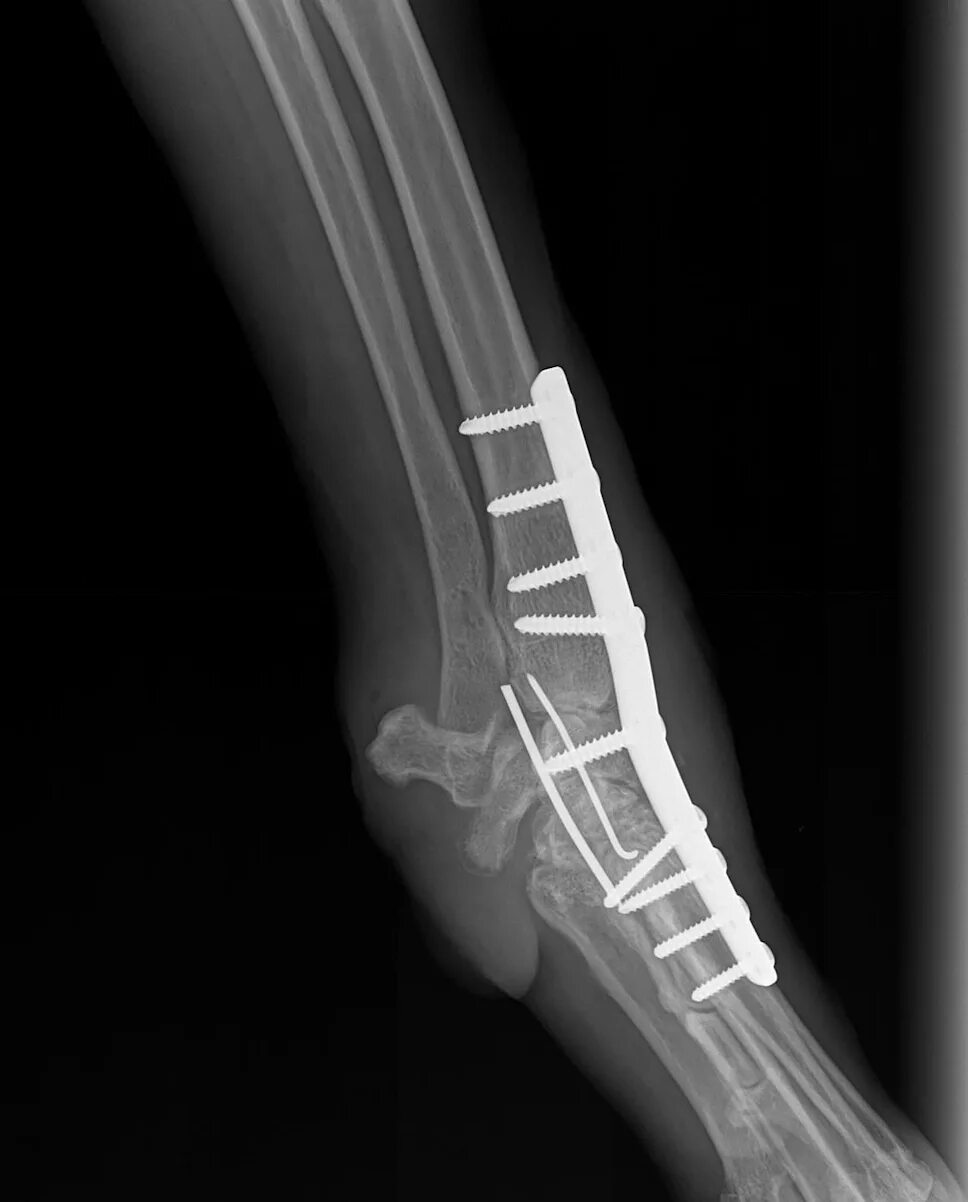

Артродез форум